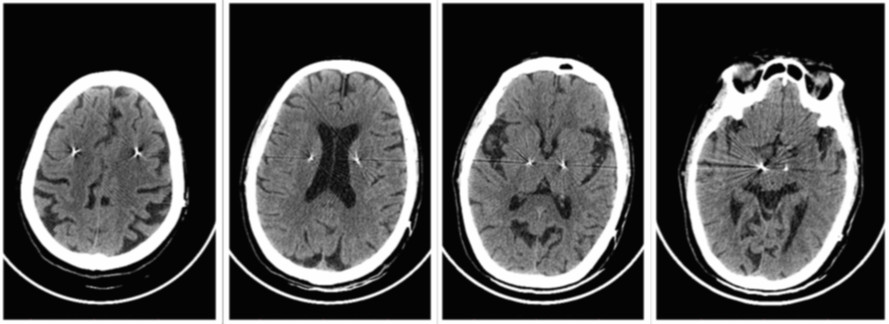

术后

头颅CT:颅内无出血、积气等,电极避开脑室系统

术后CT与术前MRI融合,电极位置准确

术后电极位置三维重建,电极触点位于STN核(lead DBS)